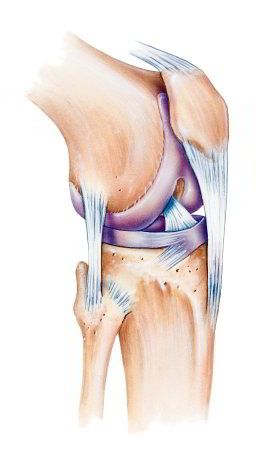

Kniescheibe mit

Bändern, Schema Seitenansicht Kniescheibe mit Bändern, Schema Seitenansicht [2] und von vorn [3]

-- die Kniescheibe ist eine etwas dreieckige Scheibe mit Wölbung zum Schutz des Knies

-- die Kniescheibe wird von Sehnen oben und unten gehalten, oben am Oberschenkelmuskel angesetzt, unten am Schienbein angesetzt

-- dank der Kniescheibe und den Sehnen kann man das Bein in leichter Weise strecken

-- die Rückseite der Kniescheibe hat eine Knorpelschicht für das Gleiten beim Beugen und Strecken des Beines

-- im Alter bildet sich die Knorpelschicht zurück, so beginnt oft eine Kniearthrose

-- Schäden an der Kniescheibe können sein: Fehlbildung, Bruch, Entzündung [web01]

Knie mit Kniescheibe mit

Bändern, Vorderansicht

Schema Knie Querschnitt

Knie Schema mit dem Querschnitt [x1]

"Die Kniescheibe (Patella) ist ein flacher Knochen, der vor dem Kniegelenk liegt. Von vorne betrachtet hat die scheibenförmige Kniescheibe eine eher dreieckige Form mit einer leichten Wölbung nach vorn. Die Kniescheibe ist in die Sehne eingebunden, die am Oberschenkelmuskel ansetzt. Sie vergrößert damit die Hebelwirkung der Sehne und sorgt dafür, dass wir das Bein mit geringem Kraftaufwand des Oberschenkelmuskels strecken können. Außerdem schützt sie das Kniegelenk. Wenn wir das Knie strecken und wieder beugen, wandert die Kniescheibe mehrere Zentimeter über den Oberschenkelknochen. Deshalb ist die Rückseite der Kniescheibe mit einer dicken Knorpelschicht überzogen. Schäden an der Kniescheibe können sich aus Fehlbildungen ergeben, durch Bruch oder Entzündungen entstehen. Außerdem beginnt eine Kniearthrose häufig an der Kniescheibe." [web01]